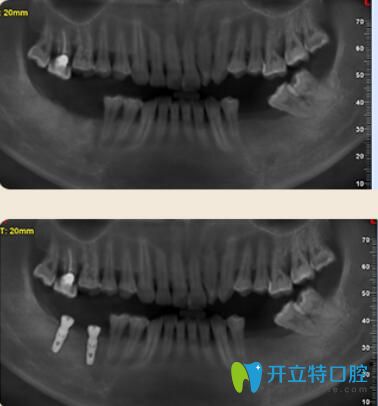

案例二:多顆牙齒缺失的胡先生種植牙案例

胡先生年齡不是特別大,但是已經(jīng)缺牙多顆,不僅影響日常飲食,對(duì)發(fā)音也有一定的影響。聽(tīng)朋友說(shuō)好佰年口腔的數(shù)字化種植技術(shù)很先進(jìn)的,于是來(lái)到了好佰年。

多顆牙齒缺失的胡先生種植牙案例

因?yàn)楹壬鷮?duì)疼痛非常敏感。所以在種植時(shí)候結(jié)合睡眠技術(shù),種牙過(guò)程中沒(méi)有任何的不適和疼痛感,半小時(shí)后種好牙齒,隨便吃,再也不用擔(dān)心吃硬東西了!

東莞好佰年口腔多顆牙種植案例